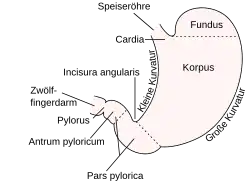

Der Pylorus (altgriechisch πυλωρός pylōrós, deutsch ‚Pförtner‘[1]), das Ostium pyloricum, der Magenausgang oder Magenpförtner ist der letzte Abschnitt des Magens zwischen dem Antrum pyloricum („Pförtner-Vorraum“) und dem Zwölffingerdarm (Duodenum). In seiner Wand bildet die ringförmig angeordnete glatte Muskulatur einen Schließmuskel, den Musculus sphincter pyloricus. Der Pylorus ist in Ruhe geschlossen. Er hat die Aufgabe, den Weitertransport des Nahrungsbreis vom Magen in den Darm zu regulieren.[2] Bei vielen Paarhufern weist der Pylorus durch Drüsen in der Submukosa und Verdickung der Ringmuskelschicht einen Wulst (Torus pylori) auf, der die Öffnung des Magenpförtners verengt.[3]